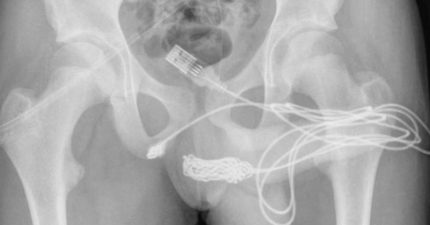

他好奇多長「整條USB線塞小弟弟」 醫驚:打結了

September 8, 2022

世界